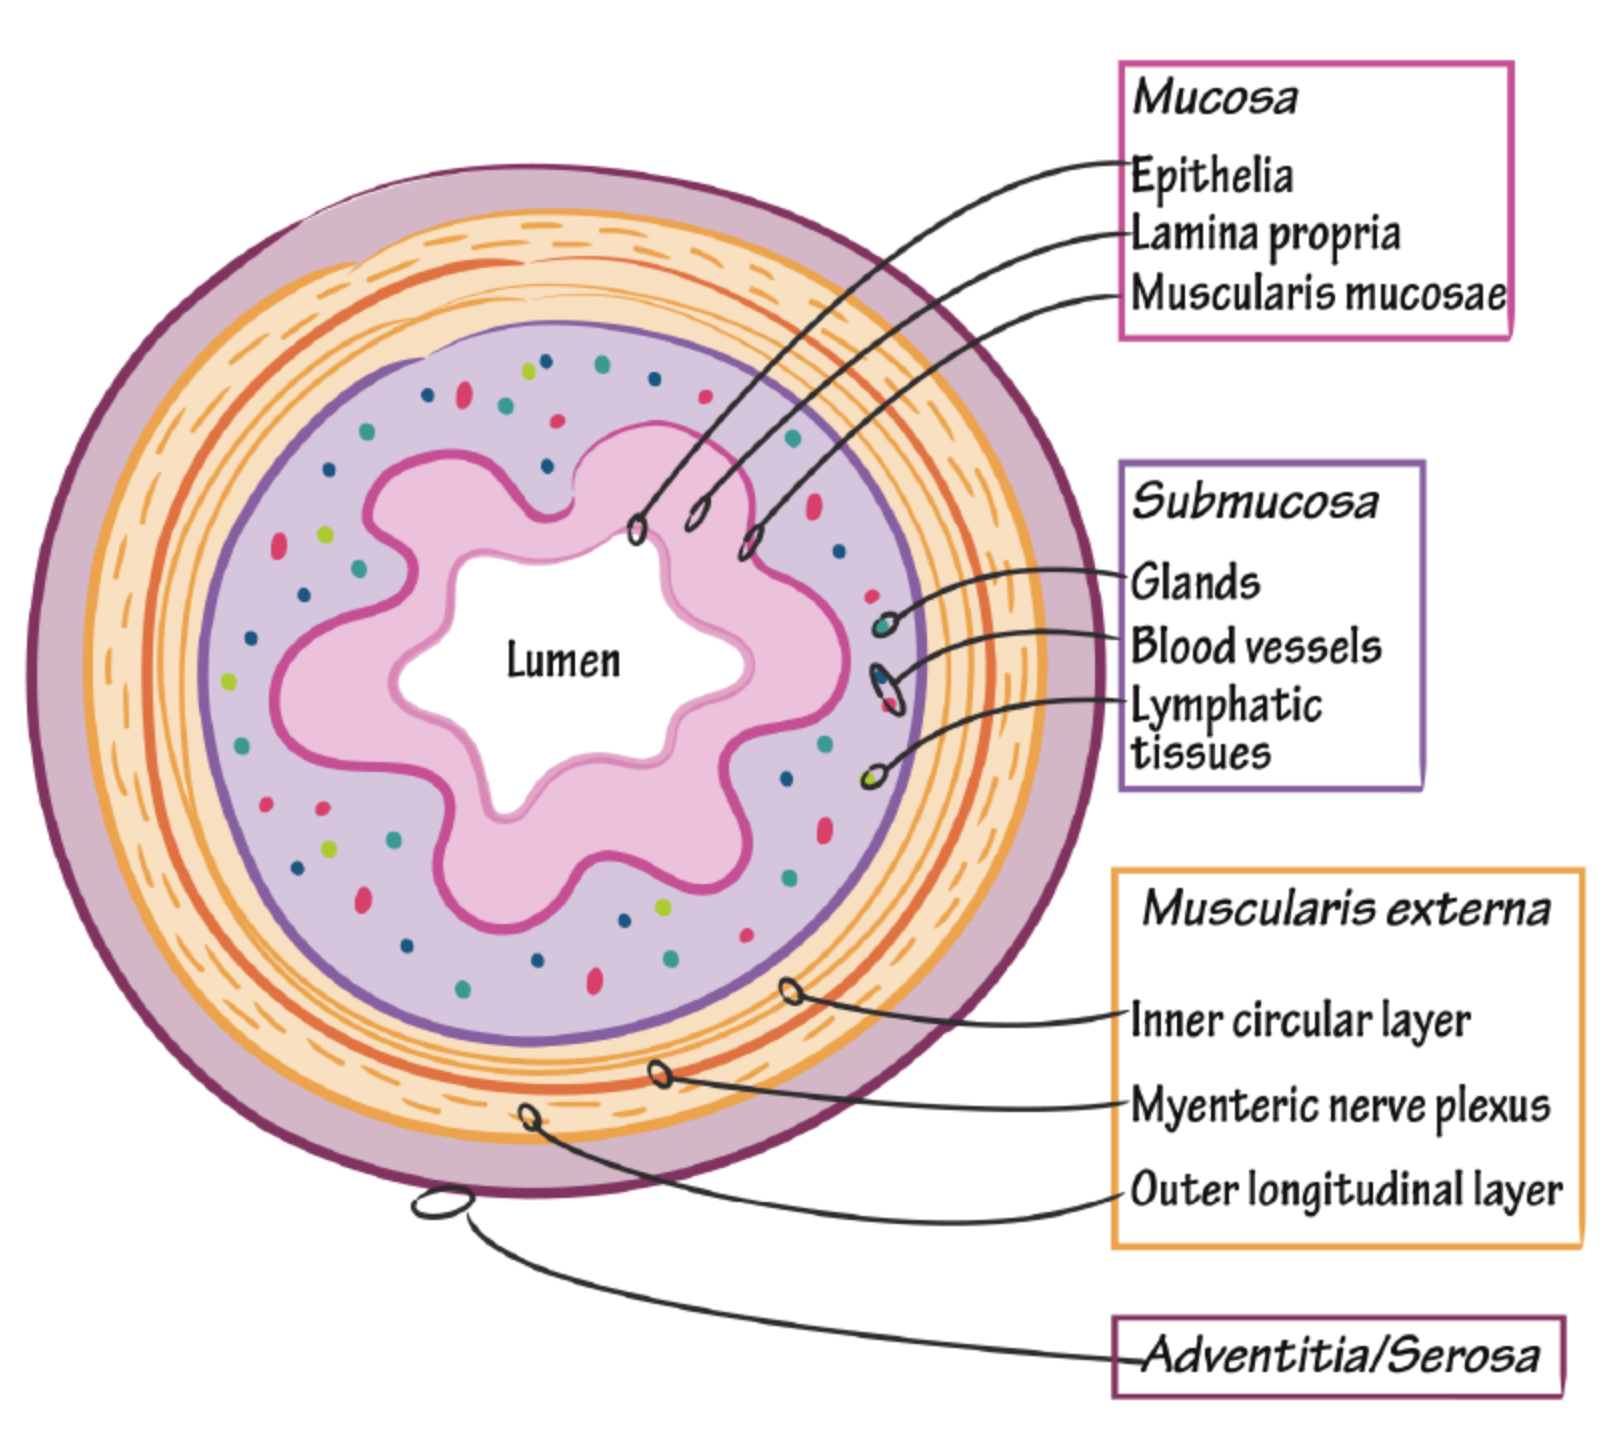

| Depth | Transmural (all layers of bowel wall) may result in ulcers, transmural ulcers, resulting in fistula formation | Mucosa and submucosa only - rarely presents as feature of fistula formation |

| Depth of Inflammation | Mucosa and submucosa | Transmural |